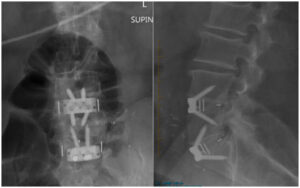

ALIF (anterior lumbar interbody fusion) is a common surgical solution for degenerative disk disease and other conditions that affect the disks in your lower back that cushion your vertebrae. In ALIF, a surgical team makes incisions in your abdomen to get access to your vertebrae so they can replace damaged disks with bone grafts that eventually make your vertebrae fuse together.

ALIF (anterior lumbar interbody fusion) is surgery to treat degenerative disk disease and other conditions that happen when damaged or worn-out intervertebral disks put pressure on your spinal nerves. Intervertebral disks are the round cushions in your spine that separate and cushion your vertebrae. In ALIF, surgeons replace your damaged disks with bone grafts, reducing pressure on your spinal nerves. These grafts eventually create new bone that fuses or joins vertebrae together.

Anterior lumbar interbody fusion is a type of spinal fusion. It gets its name from the way healthcare providers perform the operation: Surgeons access your lower back (lumbar) from the front (anterior) of your body by making an incision in your abdomen (belly) so they can insert a bone or titanium graft between your vertebrae (interbody) that will fuse or join your vertebrae (fusion).

While ALIF is minimally invasive spine surgery, it’s still major surgery. ALIF is done under general anesthesia and involves an access surgeon making an incision in your abdomen (belly) so a spine surgeon can access your lower back to remove the worn-out disk and replace it with a graft.